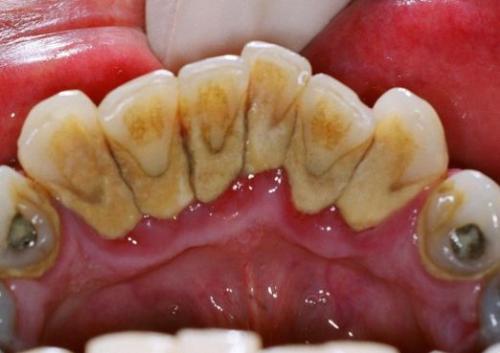

牙龈上结石是可以通过肉眼就可以看到的,一般覆盖在牙缝、牙背和牙根部。而龈下结石通过肉眼是看不见的,是由于牙结石累积过多而侵入到我们的牙龈下方,一般会伴有牙龈出血的情况。

牙结石初期呈黄色或淡黄色,时间一长就会呈现出褐色甚至是黑色。在刷牙时,可以观察牙龈上接近牙根的部位是否有明显的一层厚厚的污垢,如果有,那就是牙结石。

还有一种肉眼看不到的牙结石,它藏匿在牙龈之下。但如果你发现自己刷牙会出血,平常咬食物会出血,且又不是由于其他已确诊的口腔问题,那么多半是有牙结石了。